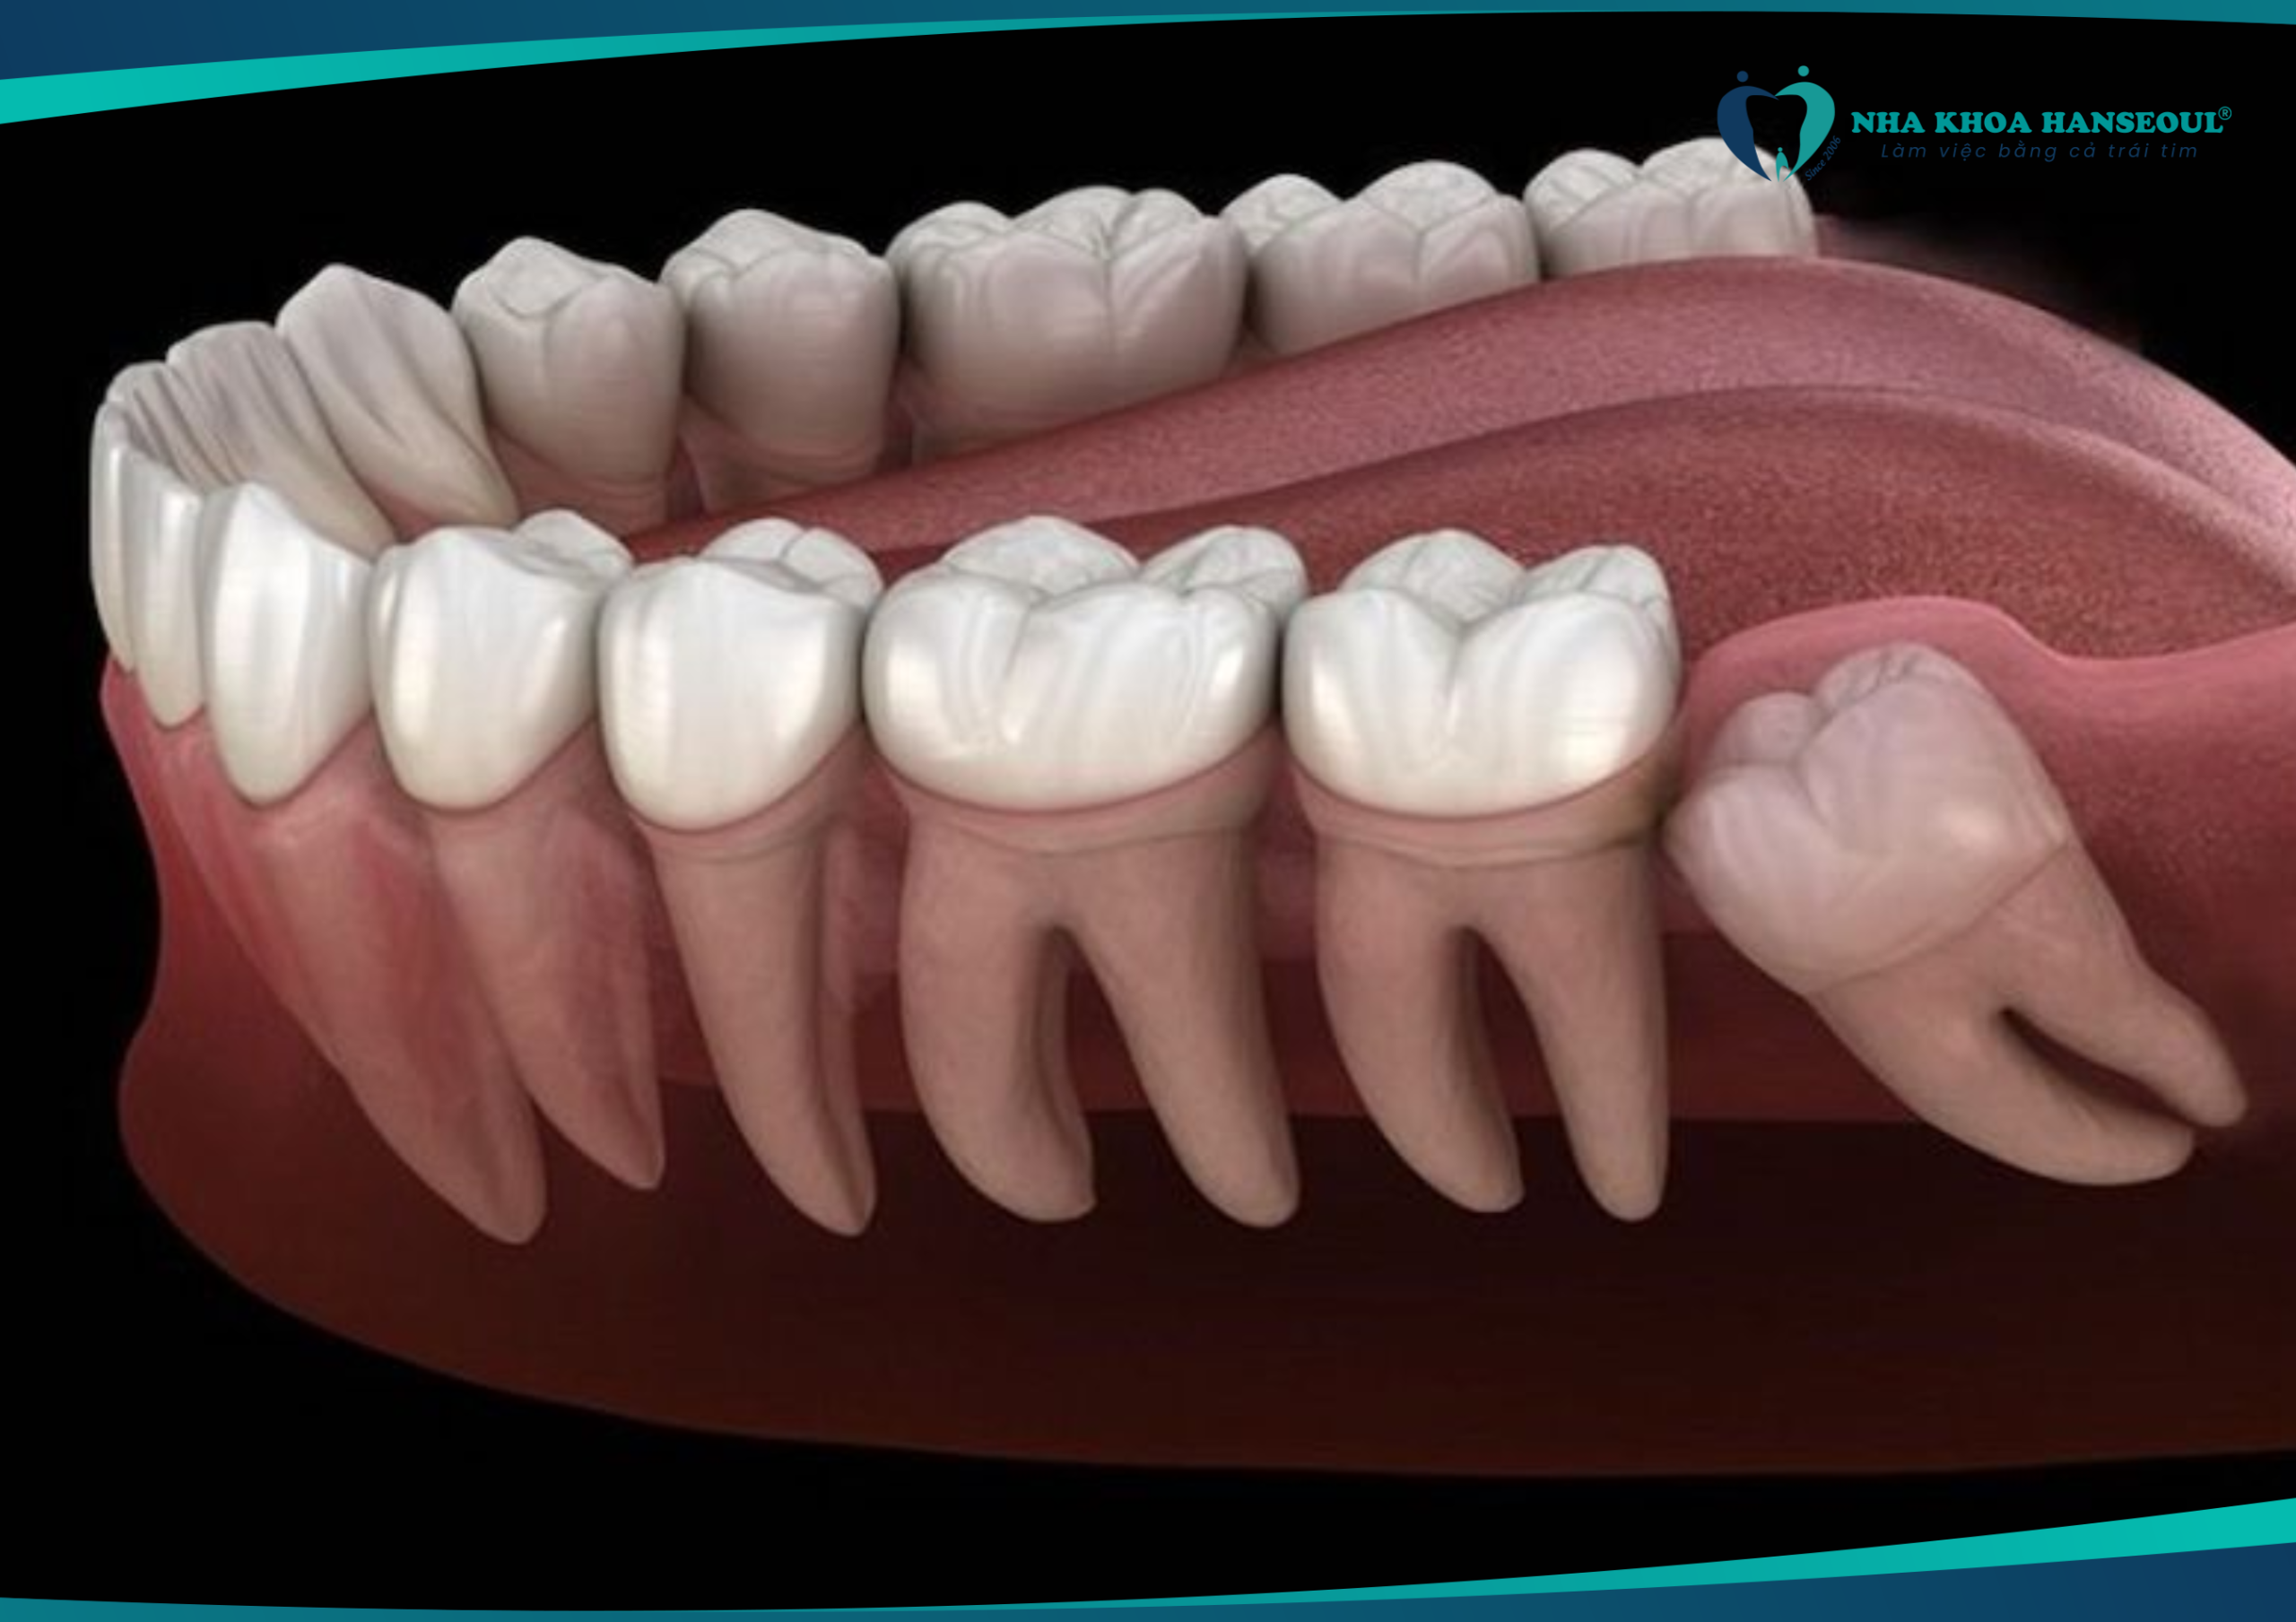

Răng số 8 không đau có nên nhổ không? Chuyên gia nói gì?